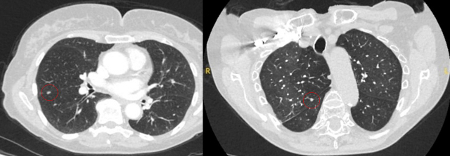

The appearance of the adjacent fissure, as well as any visible pleural ‘tags’, are signs that need to be considered when evaluating perifissural or peripheral solitary lung nodules. A retracted fissure associated with a non-smooth nodule increases the possibility of malignancy.[33][34][Figure caption and citation for the preceding image starts]: Computed tomography (CT) sections from two cases with benign perifissural nodules. Note the smooth margins and the normal undisturbed adjacent fissureFrom the collection of Dr George Tsaknis, MD, PhD, FRCP(London), MRQA, MAcadMEd, PGCert; used with permission [Citation ends].

[Figure caption and citation for the preceding image starts]: Computed tomography (CT) showing examples of malignant perifissural nodules. Note the spiculated edge of the nodules and the evident retraction of the adjacent fissure. Both resection tissue analyses confirmed adenocarcinoma of lungFrom the collection of Dr George Tsaknis, MD, PhD, FRCP(London), MRQA, MAcadMEd, PGCert; used with permission [Citation ends].